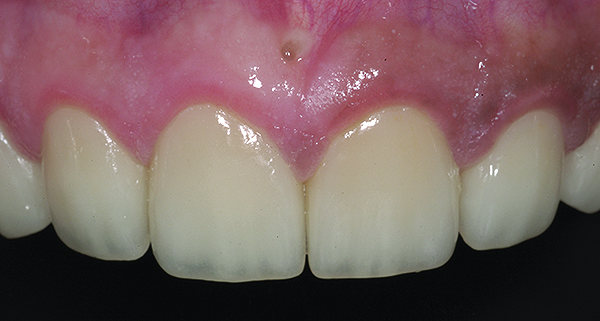

Figure 5. Preoperative 1:1 retracted frontal view.

Figure 5